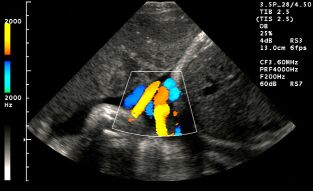

Doppler ultrasonografi

Yandaki ultrason resminde Doppler analizi sonucunda elde edilen damar şekillerini renkli olarak görüyorsunuz. Doppler, yüksek riskli gebelere uygulanan bir ileri inceleme yöntemidir. Amacı anomali taramak değil, damar akımlarını ölçmektir. Riski olmayan anne adaylarında siyah beyaz görüntüyü süslemekten başka bir işe yaramaz.